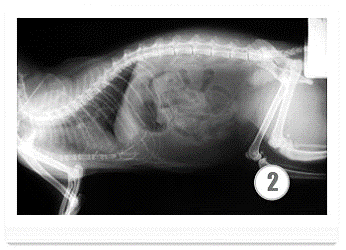

Рентгенография проводится для оценки размеров печени и выявления асцита.

артрофического цирроза. На снимке хорошо различимы увеличенная (рис 1) и уменьшенная

(рис 2) печени животных.